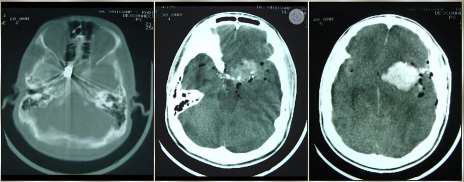

Caso Clínico 1 para as questões 21, 22, 23 e 24.

Paciente, 35 anos, sexo masculino, procedente de Recife-PE, é admitido em unidade de trauma, com história de agressão física por arma de fogo há 30 min. Veio trazido por policiais e sem profissional de saúde. Estava hipocorado, hipotérmico e possuía múltiplos orifícios de entrada de projétil de arma de fogo (PAF) em tórax, entrada e saída em região cervical e entrada em zigoma esquerdo. Apresentou parada cardiorrespiratória (PCR), revertida após 03 ciclos de reanimação cardiopulmonar, incluindo entubação orotraqueal sem sedação, expansão volêmica e drenagem torácica bilateral. Logo em seguida, após melhora hemodinâmica, não tinha abertura ocular e não tinha resposta motora, e pupilas estavam médio-fixas. De exame de imagem, fez apenas tomografia computadorizada (TC) de crânio.

Para o caso clínico mencionado acima, devem estar presentes os seguintes pré-requisitos para abertura de Protocolo de ME:

Provas